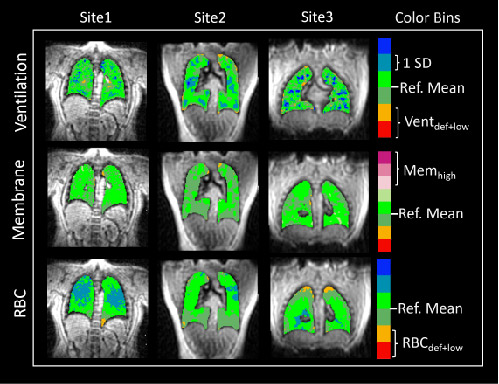

Figure 5: Correlation of Xe-MRI measures with PFTs A Defect+Low ventilation percent vs FEV1, B RBC/Membrane vs. DLCO. Black lines show the linear best fit; correlation coefficients and p values are shown on each plot. Note that points from all sites are observed on both sides of the trendline, which indicates minimal inter-site bias in Xe-MRI measures. Representative images from post-acute COVID-19 patients are shown in the bottom panel, demonstrating the heterogeneity of disease presentation.